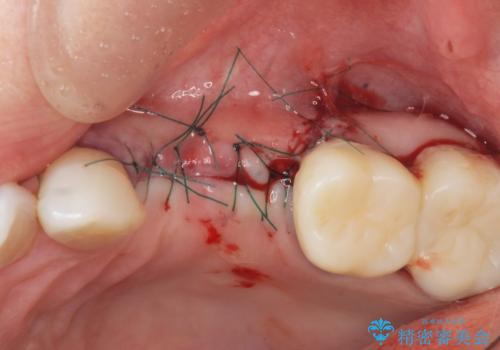

歯の穿孔(内部穴が開いている状態)破折等、歯を保存することができない問題が小臼歯には認められたので抜去を行います。

抜去後の補綴治療は長いブリッジではなくインプラント治療を希望されましたが、穿孔・破折による周囲の骨吸収をリカバリーすべく骨の造成を伴うインプラント治療を計画します。